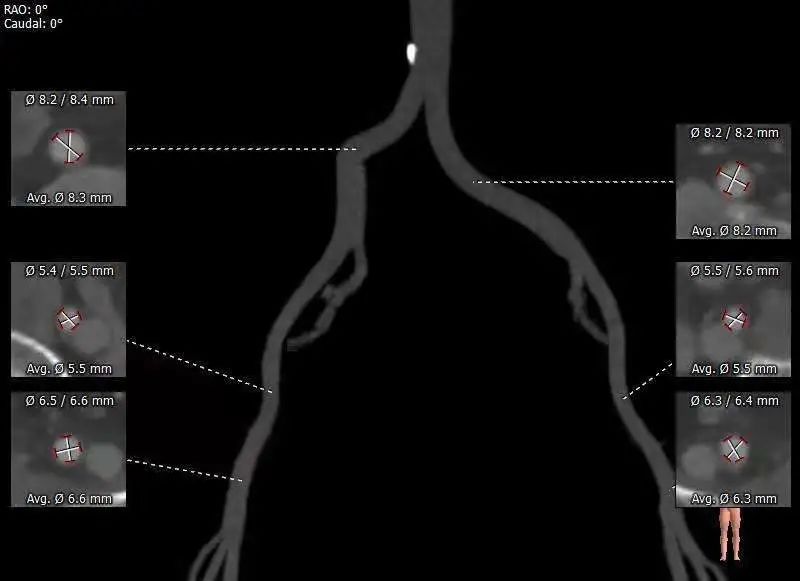

外周血管总览

外周血管入路:

推荐右侧股动脉为主入路,左侧为辅助入路。